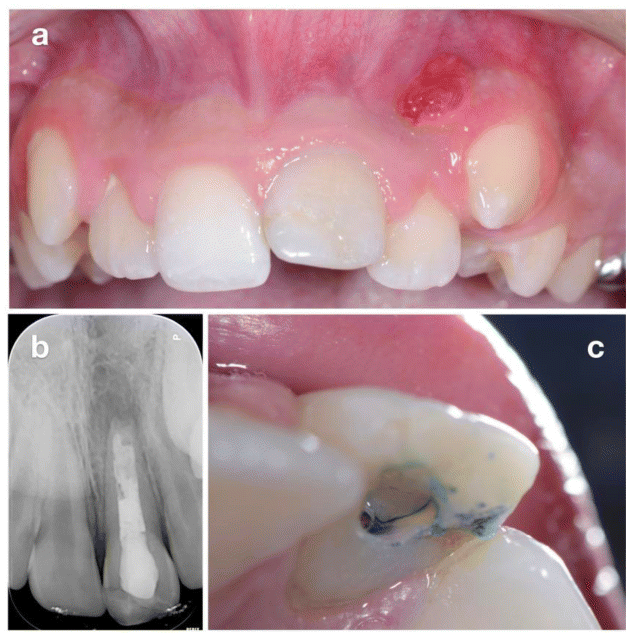

A 13-year-old male patient presented with his parents to evaluate the possibility of orthodontic treatment due to anterior crowding. Clinically confirmed anterior crowding and revealed a buccal fistula in the regions of teeth 2.1 and 2.2 (Figure 1a). The maxillary left central incisor (2.1) had sustained trauma at the age of 8, resulting in a complicated crown fracture with pulp exposure, treated at that time by apexification and coronal restoration (Figure).

Thermal sensitivity testing confirmed vitality in all adjacent teeth except 2.1. Periapical radiography demonstrated an incongruent root canal treatment, incomplete root development, and a periapical radiolucency (Figure 1b). A preliminary plan of nonsurgical endodontic retreatment was considered; however, upon re-entry, methylene blue staining revealed a vertical distal root fracture (Figure 1c). CBCT confirmed a vertical fracture of 2.1 and a large osteolytic lesion extending to 2.2, with complete loss of the interdental septum and vestibular alveolar fenestration (Figure 2).